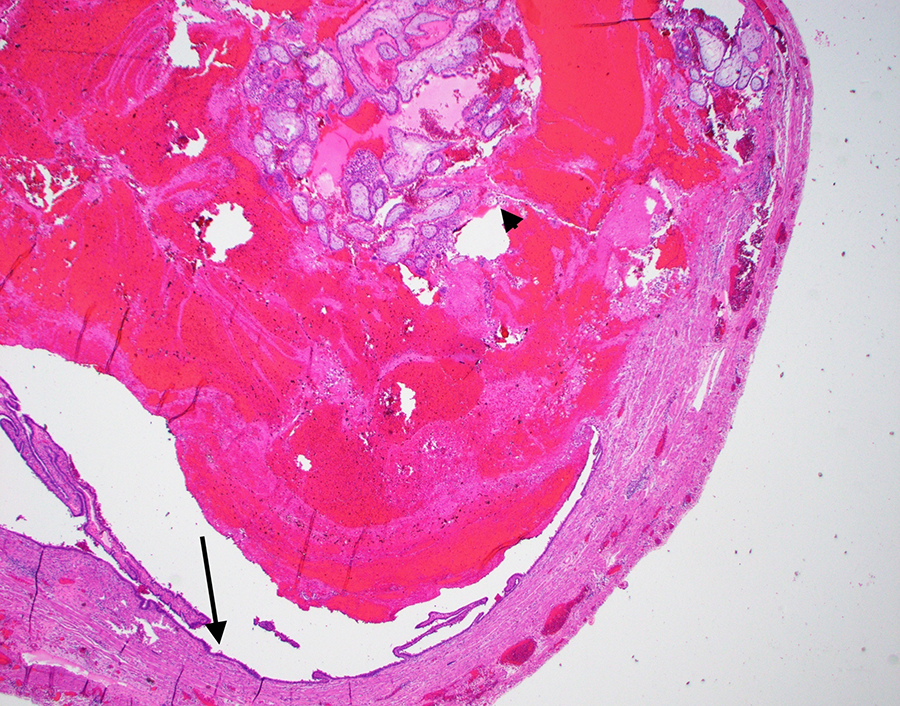

A tubal ectopic pregnancy can be grossly described as a distended fallopian tube with a thin wall, which may be ruptured, with dusky and dark serosa (Figure 3). Sectioning usually reveals hemorrhage with villous-appearing tissue. Fetal parts may be seen occasionally (Figure 4). On histology, chorionic villi associated with the fallopian tube is diagnostic of an ectopic pregnancy (Figures 5 and 6). Hemorrhage within the tubal lumen is often present.

Cross section of fallopian tube diagnostic of an ectopic/tubal pregnancy. H&E-stained section at ×20. Note the fallopian tube epithelium (arrow) and luminal hemorrhage with chorionic villi (arrowhead).